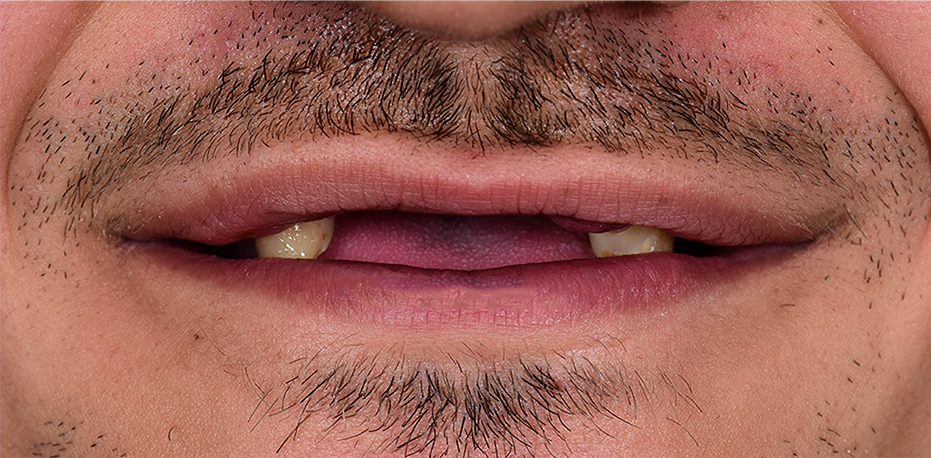

Questi sono solo alcuni casi che abbiamo risolto tra le migliaia in passato di pazienti che hanno perso i denti da malattie, incidenti stradali o errori di altri dentisti.

La maggior parte dei pazienti che arrivano nella nostra cliniche a Tirana hanno dentiere immobili o non hanno più i denti e attraverso i nostri impianti dentali . Ritrova il tuo sorriso e la felicità.